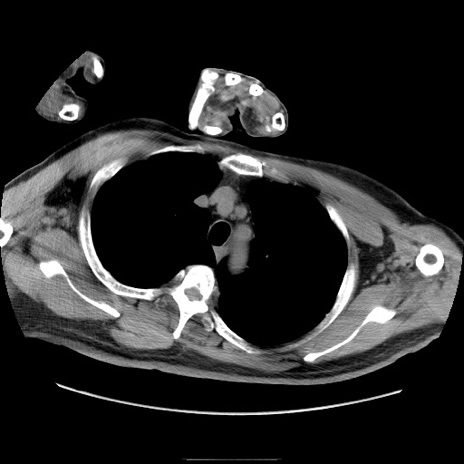

冠状断像

【症例】50歳代男性

【主訴】腹痛

【現病歴】AVMからの被殻出血のため回復期リハ病棟入院中。 本日午後3時頃急に下腹部痛が出現した。

【既往歴】AVM、被殻出血、虫垂炎、高血圧

【身体所見】意識晴明、左半身不全麻痺、会話の理解は良好、36.5°C、腹部:膨隆、全体に板状硬、下腹部正中に圧痛点あり、反跳痛-、筋性防御不明、右下腹部にope scar

【データ】WBC 9400、CRP 0.06